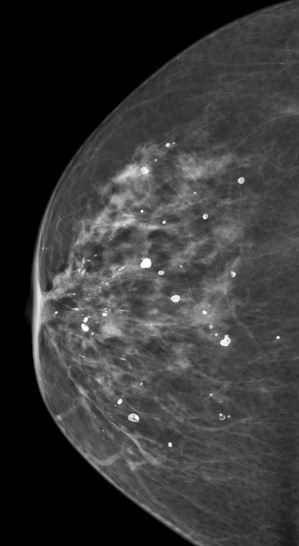

Kalsifikasi adalah endapan kalsium kecil yang dapat terjadi di mana saja di jaringan payudara. Mereka muncul sebagai titik-titik putih kecil yang lebih baik dilihat pada mammogram. Mereka jarang terlihat pada USG dan tidak pernah muncul di MRI payudara.

Fitur / pola kalsifikasi tertentu pada MMG akan menunjukkan apakah kalsifikasi tersebut mencurigakan atau tidak.

Kalsifikasi besar / makrokalsifikasi, tepi dan bentuk yang terdefinisi dengan baik dan menyebar

Bintik kecil / debu seperti / mikro-kalsifikasi, berbagai bentuk dan ukuran, berkerumun dan berjajar di sepanjang saluran